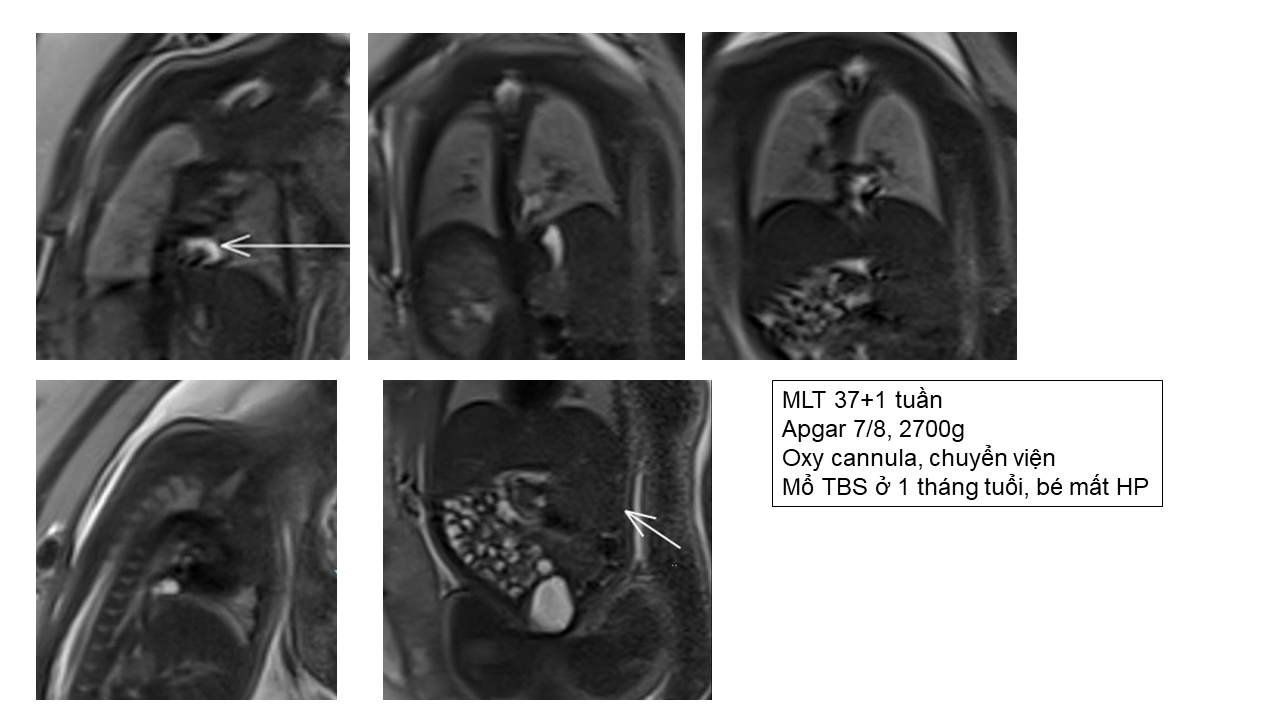

Thoát vị hoành - phải hay trái?